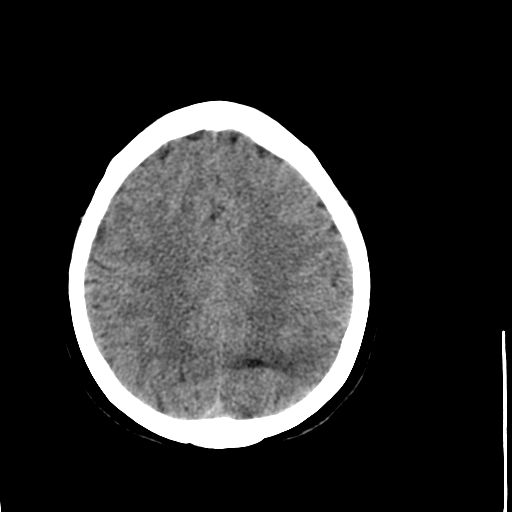

病人资料:女,57岁,反复头痛6年余,无恶心、呕吐等症状,体查:bp180/100mmhg。

中线脂肪瘤

胼胝体发育不良并脂肪瘤形成,脂肪瘤形成是因,胼胝体发育不良是果。如果正规些应该是中线脂肪瘤并胼胝体发育不良!

典型中线脂肪瘤

胼胝体发育不良

中线脂肪瘤并胼胝体发育不良。